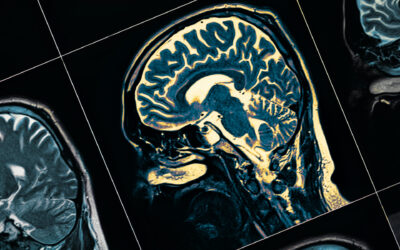

Previously, we looked at Traumatic Brain Injury (TBI). To recap, a TBI is an injury to the brain as a result of an external force, such as blow to the head. It is a complex injury with a broad...

Traumatic Brain Injury

Like with any part of the body, your brain can get injured. You may have heard this referenced under many names such as a concussion, stroke, shaken baby syndrome, cerebral contusion or a traumatic...